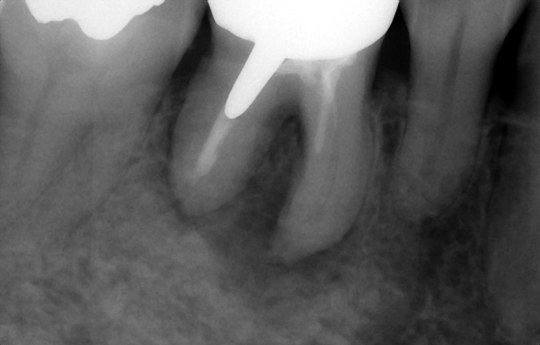

虫歯で歯が割れて周囲に強い歯周病

親知らずを移植し根管治療中

※現在治癒を経過観察中